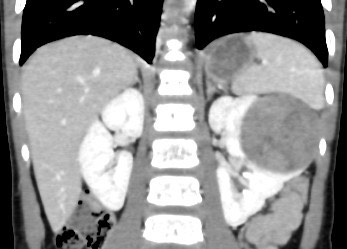

1370. Пациенту 3 лет со стойким на протяжении недели повышением температуры до 37,5⁰с выполнена компьютерная томография, патологическим процессом, соответствующим клинико-рентгенологической картине, считают